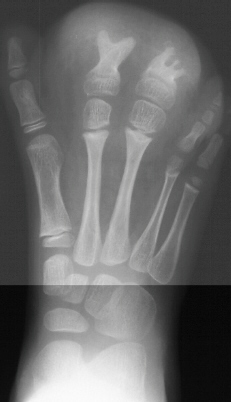

At age 12 months a girl presents severe overgrowth of the foot. She

was the product of a normal pregnancy and delivery and is otherwise completely

healthy. The parents main complaint is that she can not be fitted with

shoes. She had an amputation (image 1 & 2) of the 2nd and 3rd toes

at the level of the mid diaphysis proximal phalanx and extensor tendon

release of the 2nd and 3rd toes with excision of abnormal fibrofatty tissue